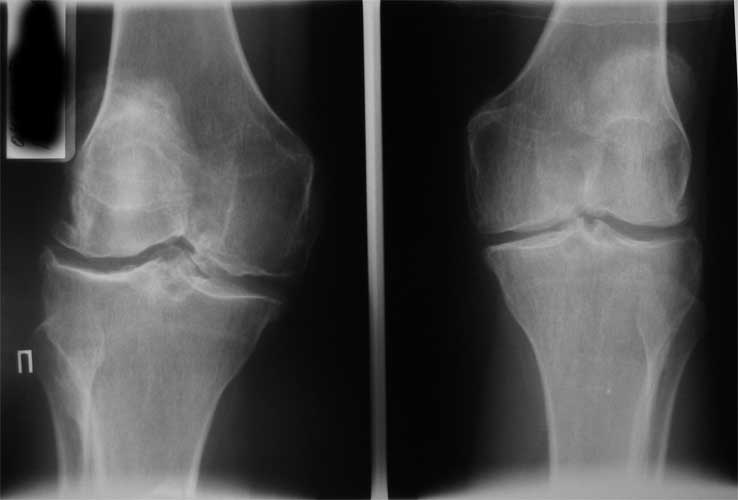

Уважаемые коллеги, пациентка 45 лет около 9 мес назад была прооперирована по поводу

правостороннего коксартроза э/п LCS Complete RP. послеоперационный период без

особенностей, объем движений в 6 мес с/р - 110/0/0. Через 9 мес после операции возник

напряженный гемартроз (без травмы, перегрузок), получено до 190 мл свежей крови, далее

фиксация в ортезе, повторные пункции. через 2 нед выписана из стационара без признаков

гемартроза. Через 2 нед аналогичная ситуация. Вопросы :причина? как лечить?